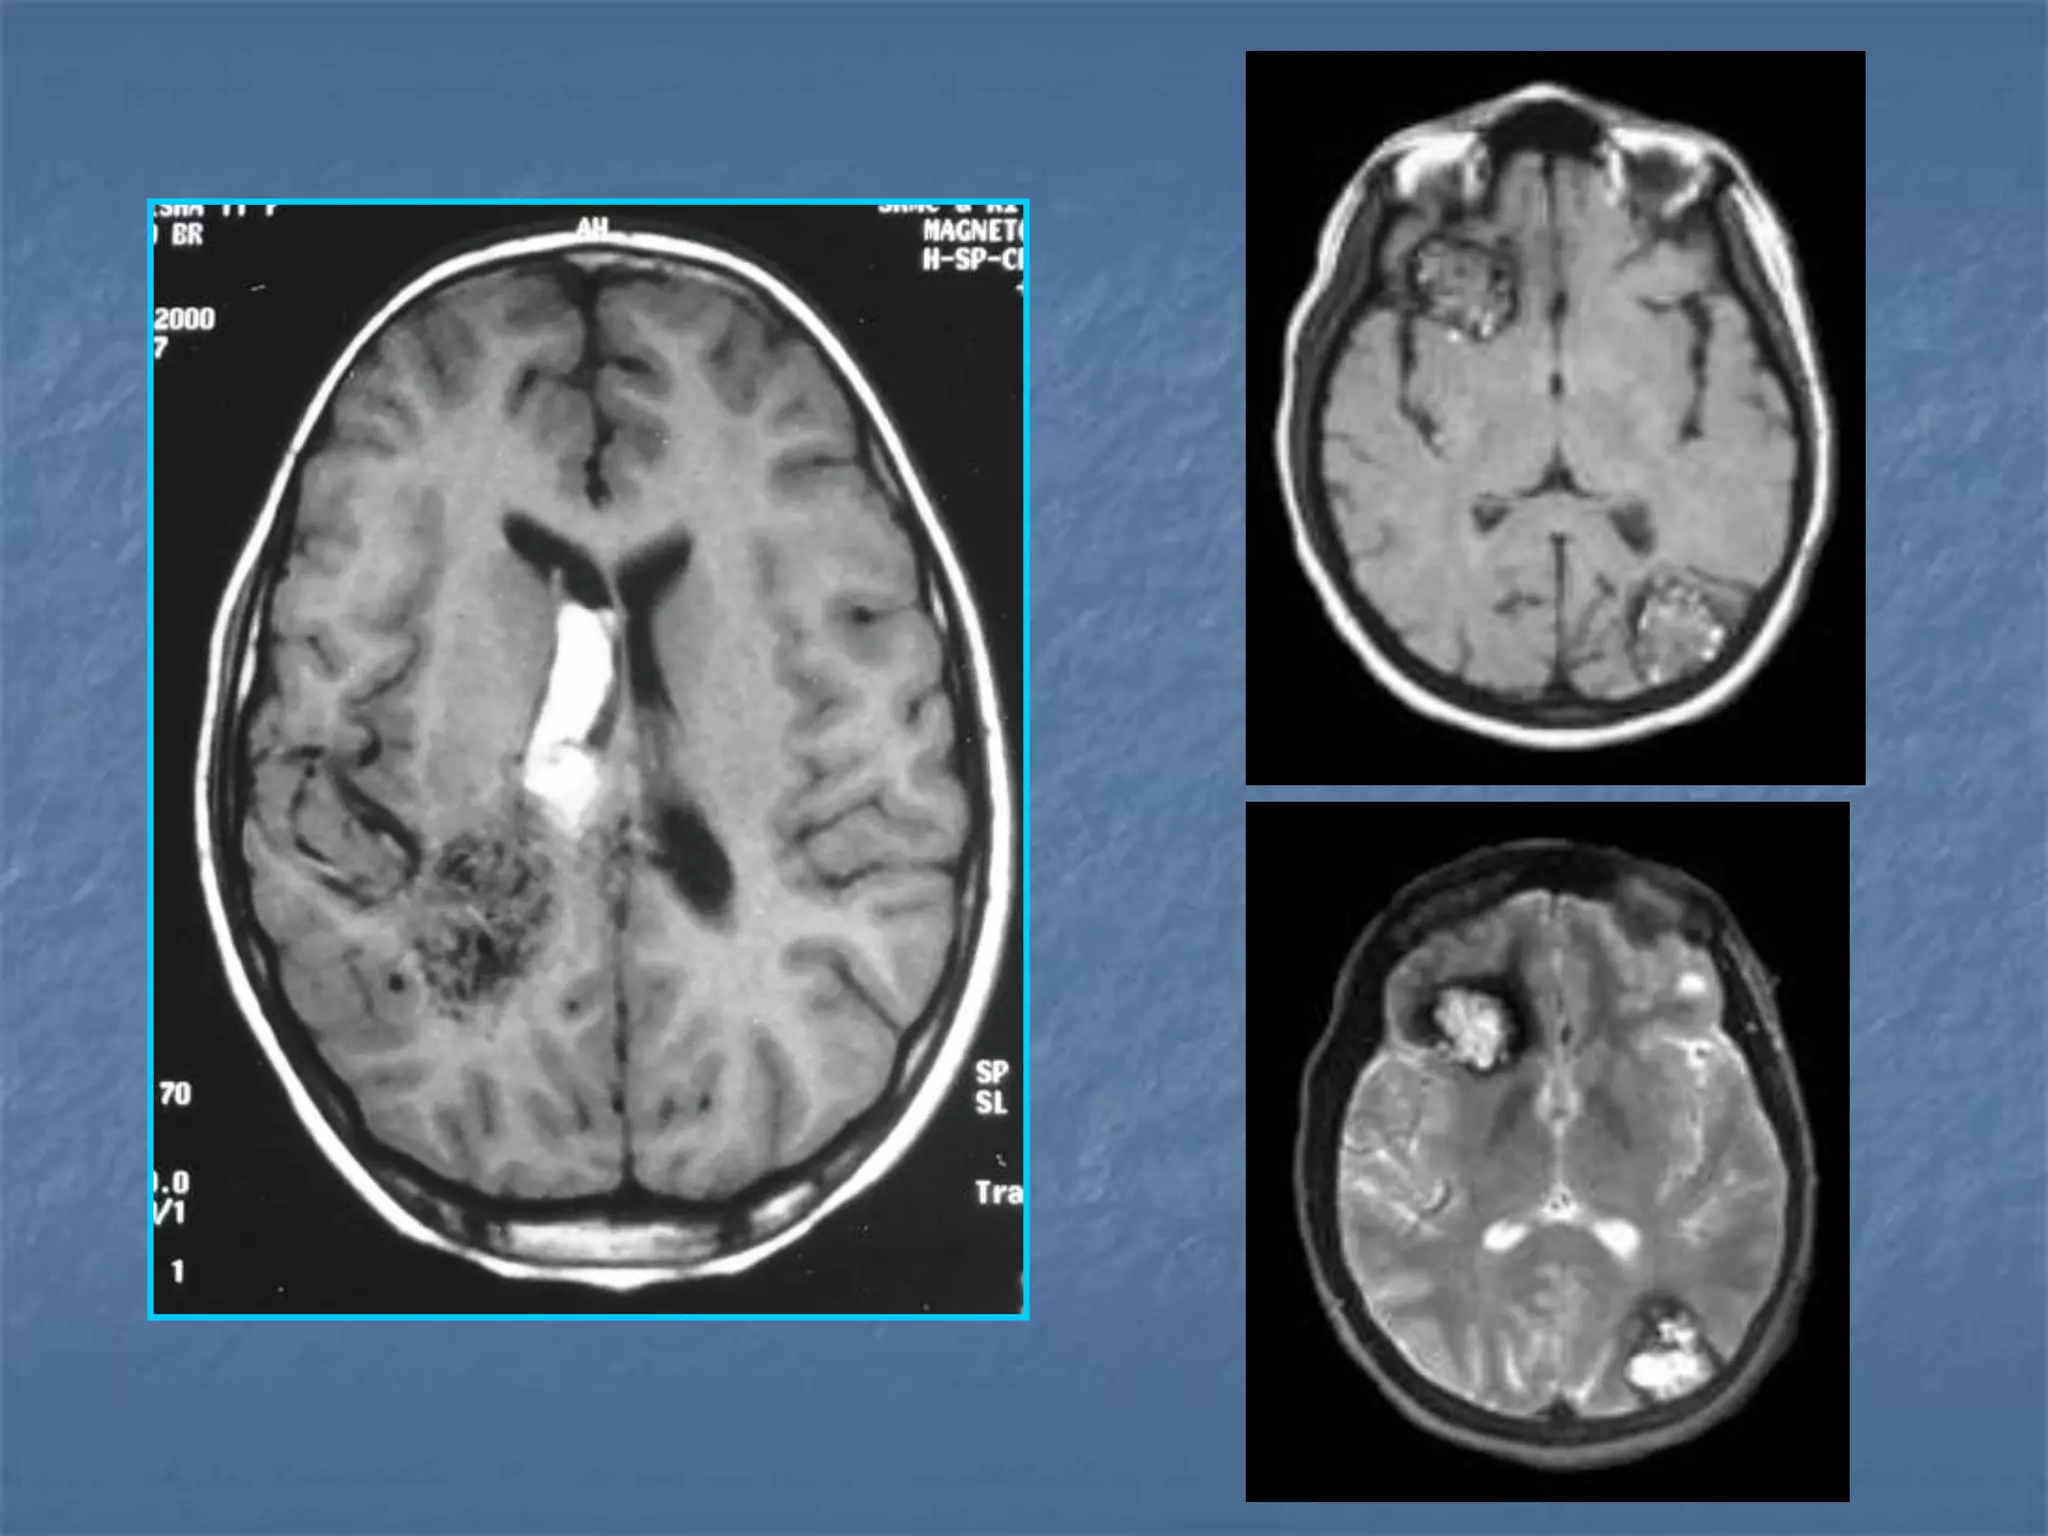

Hypertensive Hemorrhage

 Hypertensive hemorrhage accounts for

approximately 70-90% of non-traumatic primary

intracerebral hemorrhages. It is commonly due to

vasculopathy involving deep penetrating arteries

of the brain. Hypertensive hemorrhage has a

predilection for deep structures including the

thalamus, pons, cerebellum, and basal ganglia,

particularly the putamen and external capsule.

Thus, it often appears as a high-density

hemorrhage in the region of the basal ganglia.

Blood may extend into the ventricular system.

Intraventricular extension of the hematoma is

associated with a poor prognosis.